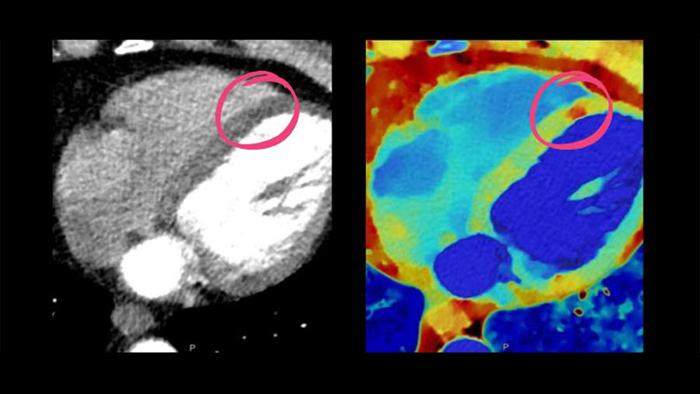

Philips Cardiac CT

Unlock the full potential of CT as a non-invasive cardiac diagnostic tool.